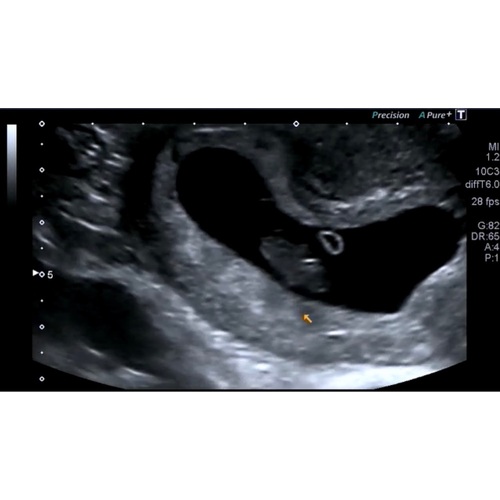

Toevallig dat dit topic nu wordt geopend, ik heb hier vanmorgen namelijk allemaal dingen over zitten opzoeken haha. Maar hoe ik het begrijp (ook op dat andere grote algemene topic gelezen), is het zo dat je moet kijken waar je placenta ligt ten opzichte van het kindje. Je ziet op vroege echo’s nog geen placenta, dus dan moet je kijken naar waar het dooierzakje ligt.

Inwendige echo: placenta/dooierzakje links = meisje, rechts = jongen

Uitwendige echo (is in spiegelbeeld): placenta/dooierzakje links = jongen, rechts = meisje

Volgens die theorie zou ik denken dat ik een meisje krijg, want dooierzakje ligt rechts en het is een uitwendige echo. Maar ik weet het ook allemaal niet zeker, dus als iemand wat anders denkt, hoor ik het ook graag 😊